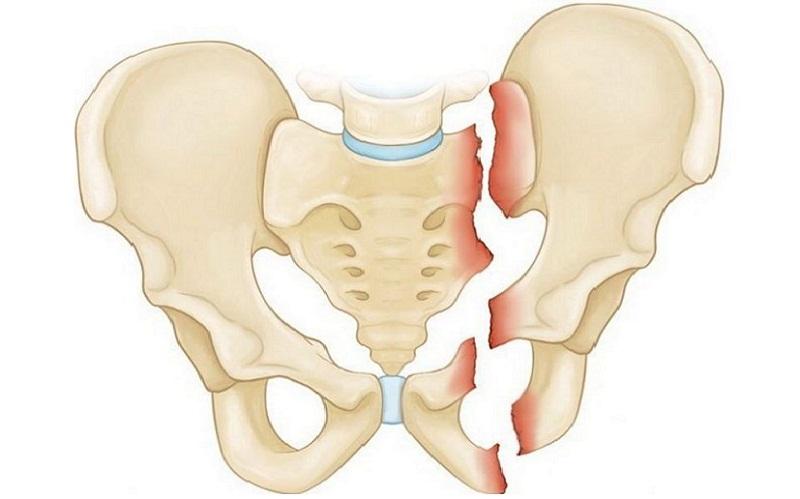

Односторонний перелом седалищной и лонной костей таза

Двусторонние переломы лонной и седалищной костей